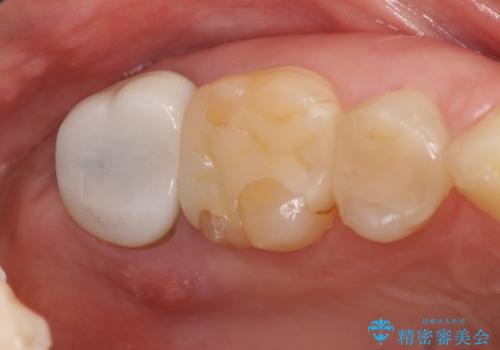

- 右上6、7の詰め物、被せ物を治して欲しいといらっしゃった方の症例です。

右上6は虫歯を除去し、右上7は再根管治療後、オールセラミッククラウンによる補綴を行いました。